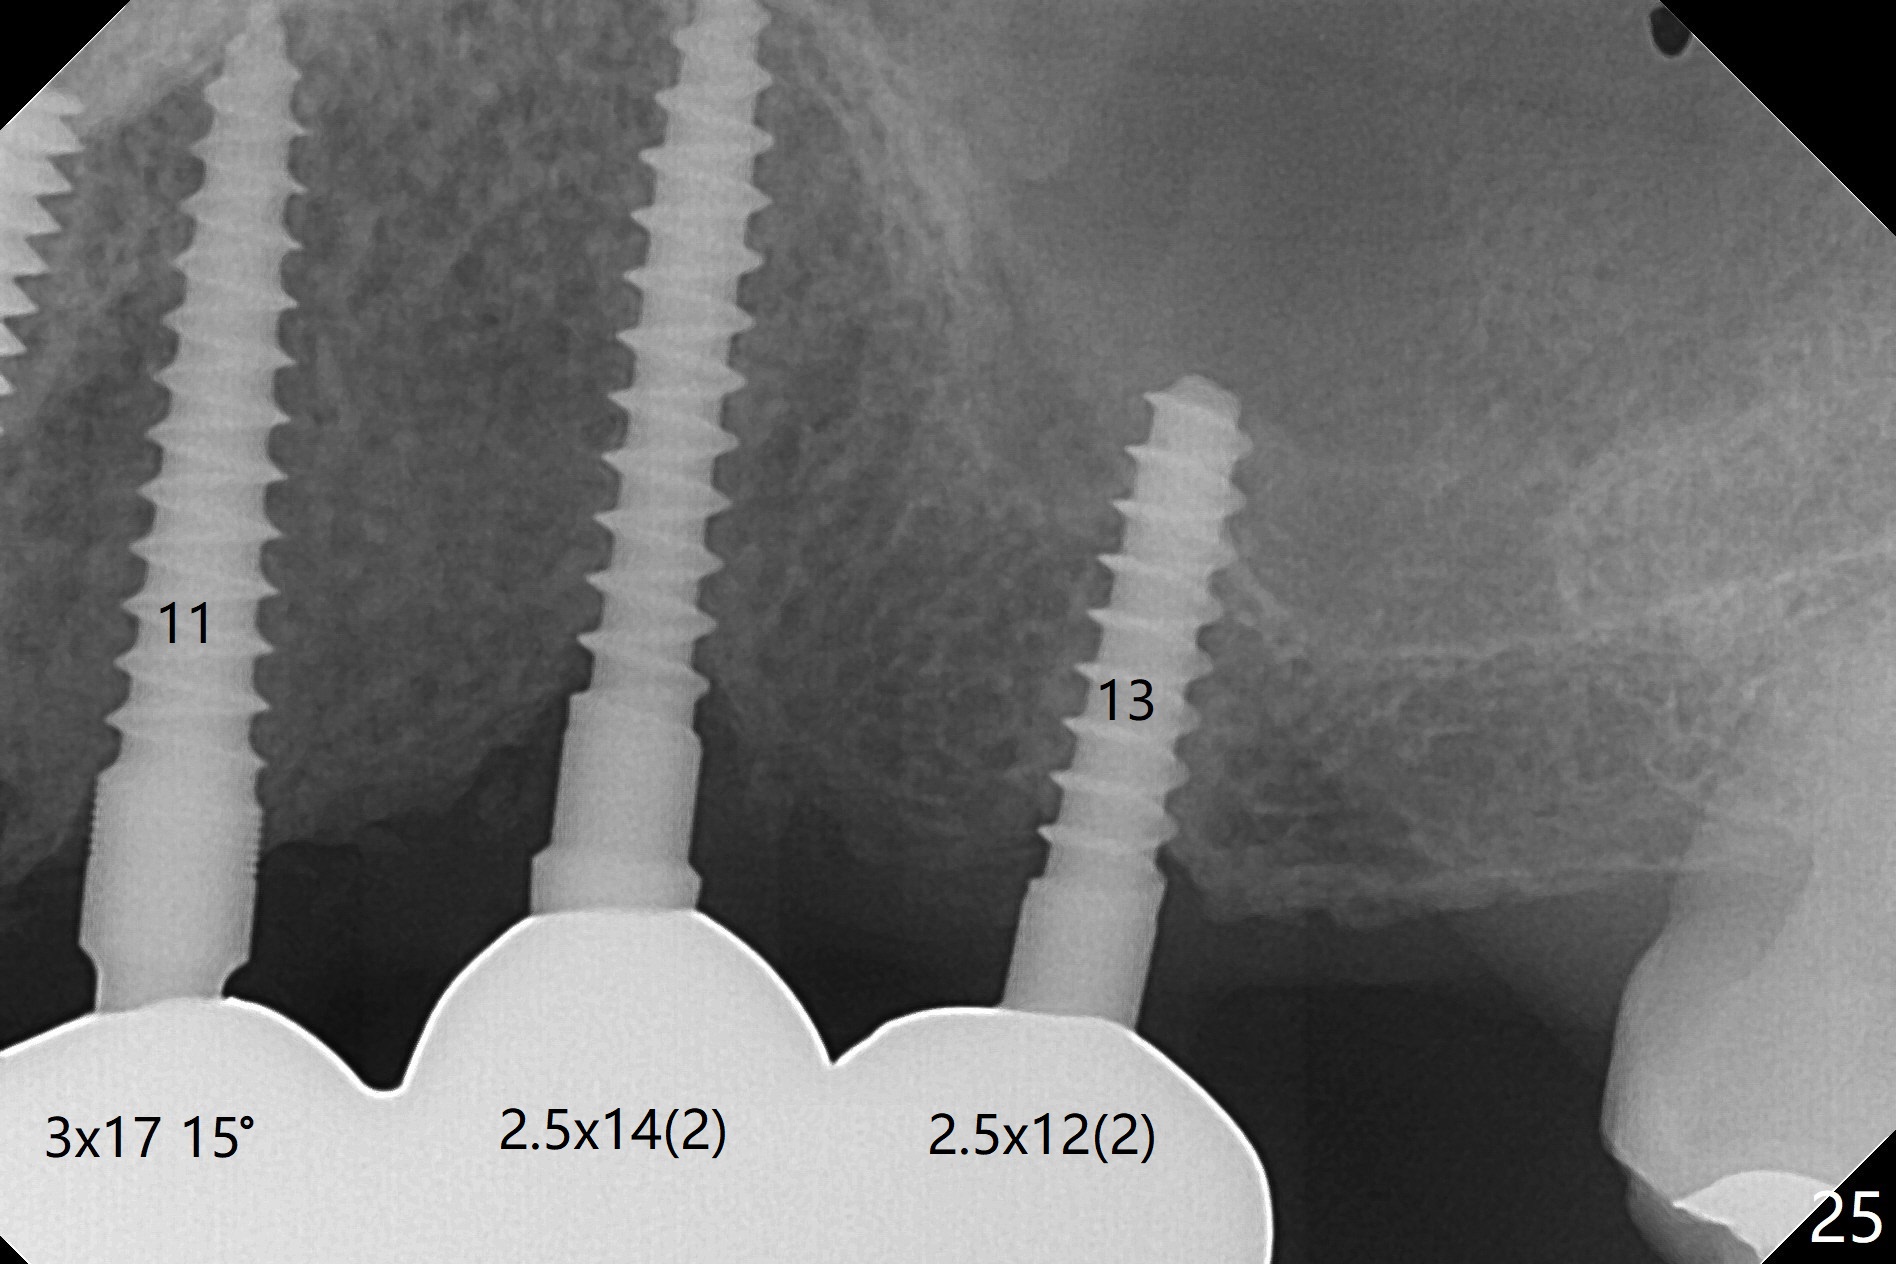

When the patient returns for implant placement (2nd visit after initial exam), he reveals that he is a dental phobic.  He requests placement of 4 implants in the upper left quadrant, instead of 2.  Narrow ridge is unexpected in the canine and premolar area (Fig.1).  Limited bone height at #13 (Fig.3 arrowheads: sinus floor) is found when initial drills are in place (Fig.2,3).  A 2-piece implant (4.5x17 mm tissue-level) is placed at #10 after extraction, while 1-piece implants are placed at 11 (3x17 mm (tissue-level, 15 °) and 12 and 13 (bone-level, 2.5x14, 12 mm, respectively; Fig.4,5).  In fact the 1 piece implant at #13 is not completely placed (Fig.5).  It is removed, the apical 3 threads are cut off (Fig.6 <, since a shorter implant was unavailable in the office) and the remaining implant is re-inserted.  The insertion torques of the 4 implants are ~ 60, ~ 35, < 35 and 15 Ncm, respectively.  After adjustment (Fig.7), immediate provisionals are fabricated at #10 and 11 (Fig.8, later splinted with composite), while perio dressing is applied around the implants at #12 and 13 and the provisionals at #10 and 11.  There is no nasal hemorrhage postop.  Although the perio dressing is loose 1 week postop (Fig.9), it is not removed.  When the upper lip fissure (Fig.9 <) heals, provisionals at #12 and 13 are planned to be splinted to the other two ones.  Two weeks postop, the upper lip fissure heals, the perio dressing dislodges and the implants at #12 and 13 are stable (Fig.10).  After abutment height adjustment, a splinted provisional is fabricated over these 2.5 mm 1-piece implants (Fig.11).